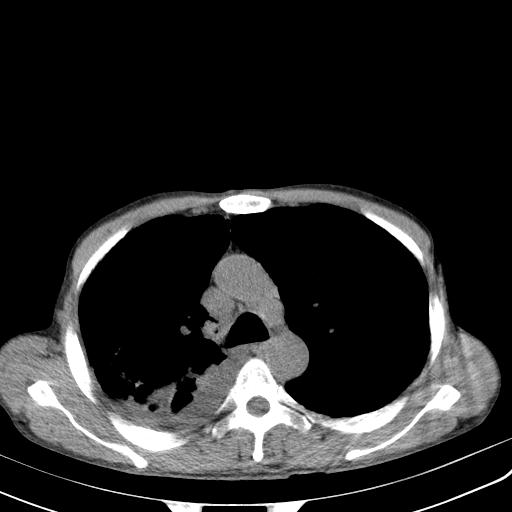

男性 75  咳嗽 一周前发热最高达39

右肺继发型tb并右侧tb性胸腔炎,右侧胸腔大量积液并右下肺膨胀不全,慢支肺气肿、多发肺大泡。建议抽胸水实验室检查并复查排除恶性在占位。

右上肺继发型肺结核,右胸腔中等量积液。

结核的基础上有纵隔淋巴结肿大,右侧有胸水,但右侧纵隔反而窄,说明有肺有不张。

再就是右下肺有块影,和不张混合,还是不能除外肺癌。

补充材料,患者2月份ct片大致正常,双侧胸腔积液,2月份抽胸水未发现ca细胞,现患者发热,痰多,各气管通畅,

1)右肺继发型肺结核。2)左肺胸膜下多发性肺大泡。3)右侧胸腔积液。